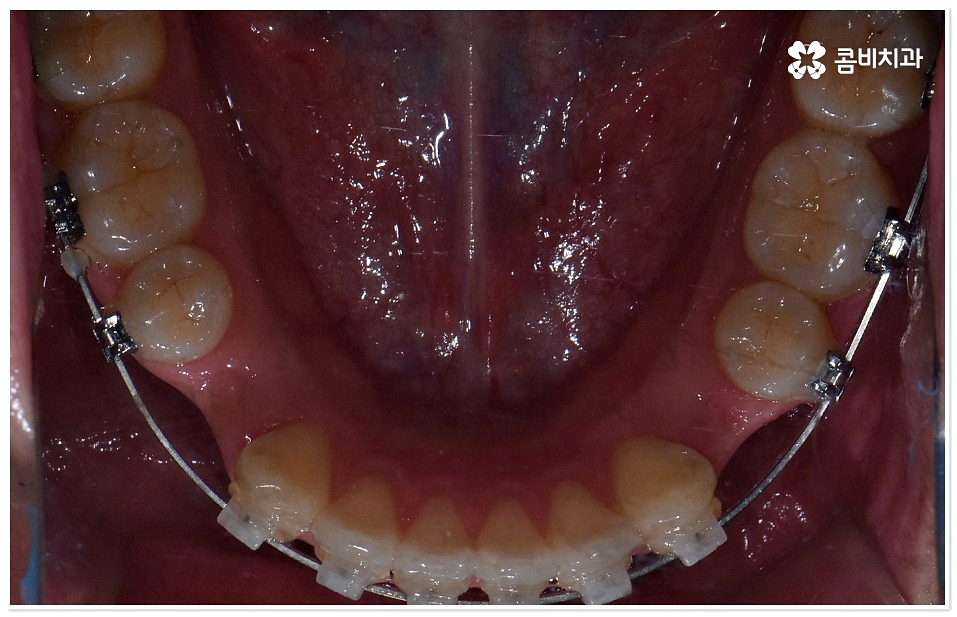

하지만 막상 덧니치아교정 을 받고 싶어도 실제로 시작하기까지 여러 가지 망설여지는 포인트가 있으실 거예요. 그 중에서도 겉으로 드러나는 장치 때문에 부담을 느끼시는 분들이 있을 수 있는데 최근에는 관련 의료 기술이 발전하면서 교정 장치가 눈에 덜 띄도록 하는 방법과 장치들이 나와 환자분들이 느끼시는 심미적인 부담을 줄여주고 있으니 먼저 검진 및 상담부터 받아보시길 권유드리고 있어요. 특히 교정치료 기간 동안 스스로 탈착이 가능한 투명교정 등 환자의 상태에 맞춘 다양한 방법을 알아볼 수 있으니 숙련된 의사선생님과 충분히 상담한 후 자신에게 적합한 계획을 세우실 필요가 있어요.

교정 치료란 특수한 장치를 이용해 치아를 원하는 방향으로 이동시켜 치아 배열과 교합을 올바르게 개선해 주는 과정으로 각자의 구강 구조가 다 다르기 때문에 정밀 검사를 통해 환자분들 각각의 치아 모양과 각도, 위치, 교합 뿐 아니라 잇몸 건강 상태 및 상악과 하악의 관계와 같은 구강 내 상황과 함께 입술, 전체 안모 등 대칭과 균형의 측면에서 모든 부분을 다각적이고 입체적으로 분석한 후 세밀한 맞춤 계획을 수립하는 것이 중요할 수 있는데요.